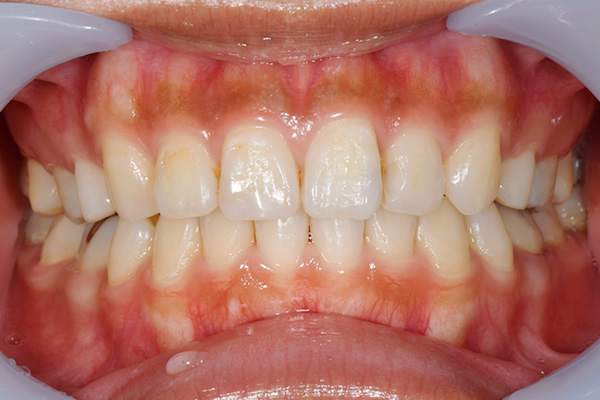

症例1

治療前

治療後

| 年齢・性別 | 30歳・男性 |

|---|---|

| 主訴 | 歯ぐきの色が気になる |

| 治療内容 | 治療費:ガムピーリング・上下顎11,000円 |

| 治療回数 | 1回30分 |

| リスク・副作用 | ピーリング後は一時的に歯ぐきの色が白くなりますが、10日程度で健康的な歯ぐきになります。痛みには個人差がありますが、やけどをしたようなヒリヒリ感を感じることがあります。 黒ずみが濃いなどの理由でご希望のお色味にならない場合は何度か施術を受けていただく必要があります。 |